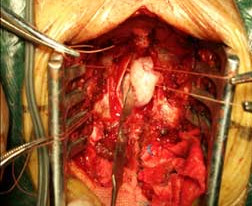

動(dòng)脈瘤夾閉術(shù)前 動(dòng)脈瘤夾閉術(shù)后